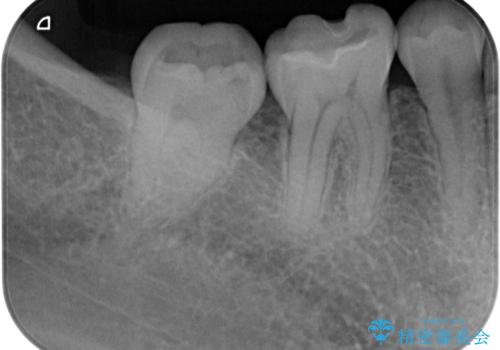

- 右下が黒くなってるとのことで来院された患者様です。レントゲン撮影により虫歯を認め、神経の反応の試験を行い正常な結果を得られたので、セラミックインレーによる修復治療を行っていくことにしました。